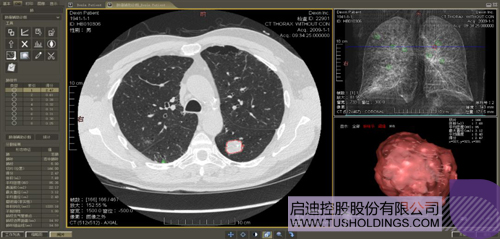

數(shù)字肺產(chǎn)品肺癌計算機輔助診斷

醫(yī)療影像智能分析是指運用人工智能技術(shù)、計算機視覺技術(shù)以及計算幾何技術(shù)對醫(yī)療影像進(jìn)行自動分析,幫助醫(yī)生定位病癥、分析、跟蹤病情,并通過量化數(shù)據(jù)輔助醫(yī)生做出診斷,目前其旗艦產(chǎn)品“數(shù)字肺”已經(jīng)覆蓋多種肺部疾病的早期檢測、診斷、跟蹤、術(shù)前規(guī)劃等完整的醫(yī)療流程。在臨床實踐中,超過80%的醫(yī)療數(shù)據(jù)來自醫(yī)療影像,這些影像數(shù)據(jù)通常需要專業(yè)醫(yī)生進(jìn)行解讀,工作的重復(fù)性高、效率偏低。如果能夠運用智能影像分析技術(shù),同時結(jié)合臨床表現(xiàn)以及既往病例進(jìn)行全面分析,那么就可以大幅度提升影像診斷效率和準(zhǔn)確性,讓專業(yè)醫(yī)生的寶貴時間集中在復(fù)雜病情的診斷和治療等環(huán)節(jié)。

數(shù)字肺——肺結(jié)節(jié)手術(shù)規(guī)劃系統(tǒng)